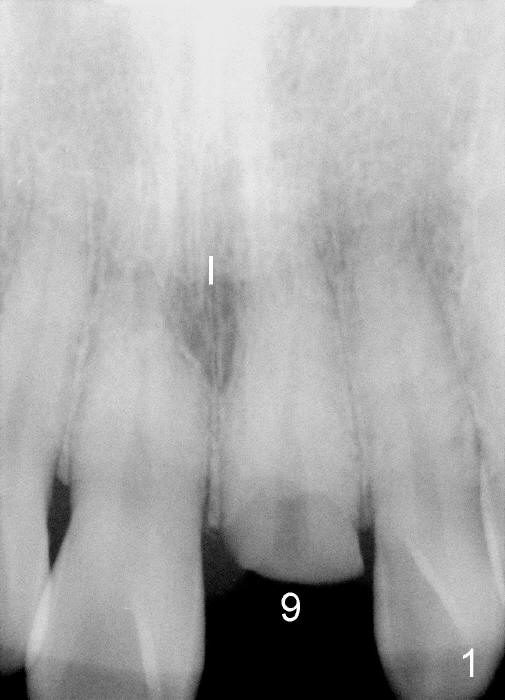

The upper right central incisor (Fig.1: #9) fractures subgingivally due to trauma for a 40-year-old man. The incisive canal is large (I) and close to the root of the central incisor. After extraction, the osteotomy (Fig.3b, 4: O) is made with 2 mm pilot drill (Fig.2: D) on the lingual wall (Fig.3a: L) of the socket (Fig.3a: S). To push the incisive canal mesially, the osteotomy is enlarged by 3.5x21 mm and 4x21 mm tapered osteotomes (Fig.5,6: O). Due to the lingual slope (Fig.7a arrow), the osteotome (blue outline) starts to deviate bucally. To reduce this tendency, the coronal portion of the lingual slope is removed (Fig.7b: yellow circle). The final implant (4.5x20 mm) is able to be placed as lingually as possible (Fig.7c, 8).

Bone expansion allows the implant (Fig.9 I) to have primary stability (insertion torque between 50 and 60 Ncm), since the cortex of the incisive canal is apparently intact. Allograft is placed in the labial gap (Fig.10, 11 *) following installation of the abutment (A). Finally an immediate provisional (Fig.10,12 P) is cemented. Fig.13,14 are taken 8 days postop. The patient returns 3 months postop (Fig.15,16). Osteointegration appears to have occurred (Fig.15 arrowheads) and is more obvious 9 months postop (Fig.17).